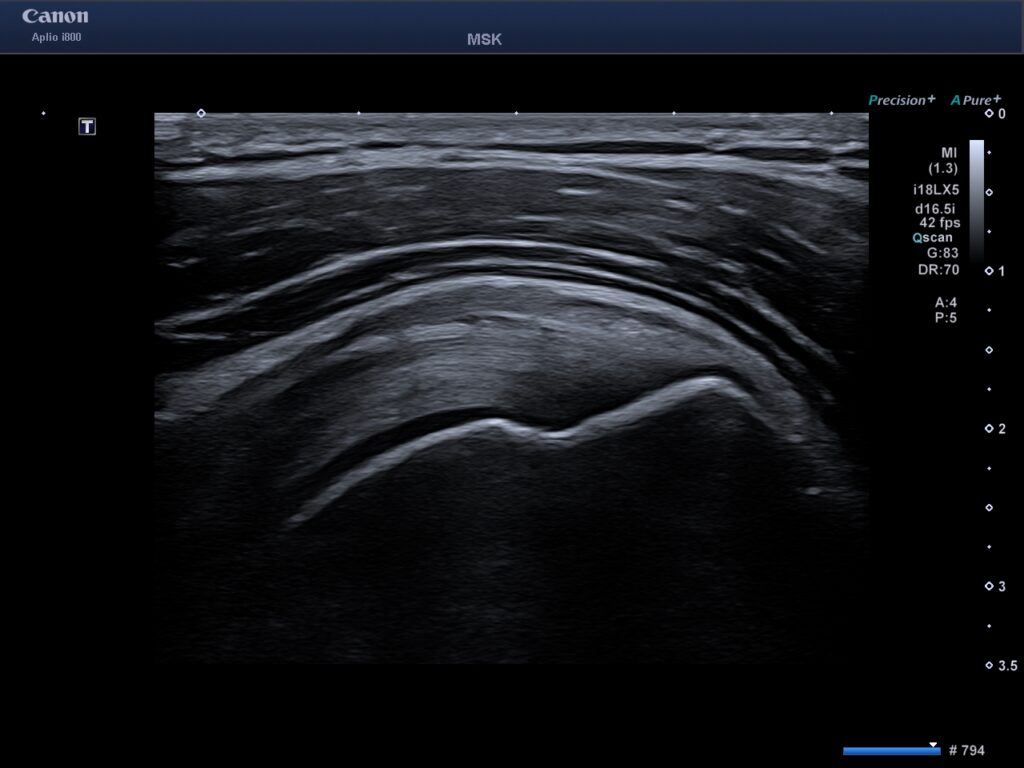

Att undersöka axeln med ultraljud är ofta det mest effektiva sättet att ställa en diagnos vid mjukdelsskador. Till skillnad från en vanlig röntgen ser vi senor, muskler, ligament och slemsäckar i realtid.

- Impingement (Inklämning): Genom en dynamisk undersökning ser vi vad som händer i axeln när du lyfter armen.

- Dynamisk undersökning: Vi kan röra på din axel samtidigt som vi filmar insidan. Det gör att vi ser besvär som inte syns när du ligger stilla i en MR-kamera.

När du kommer till oss i Göteborg börjar vi med en klinisk undersökning där vi testar din rörlighet och styrka. Därefter appliceras en gel på axeln och vi för ultraljudssonden över området. Bilderna visas direkt på en skärm där din behandlare förklarar vad som syns.